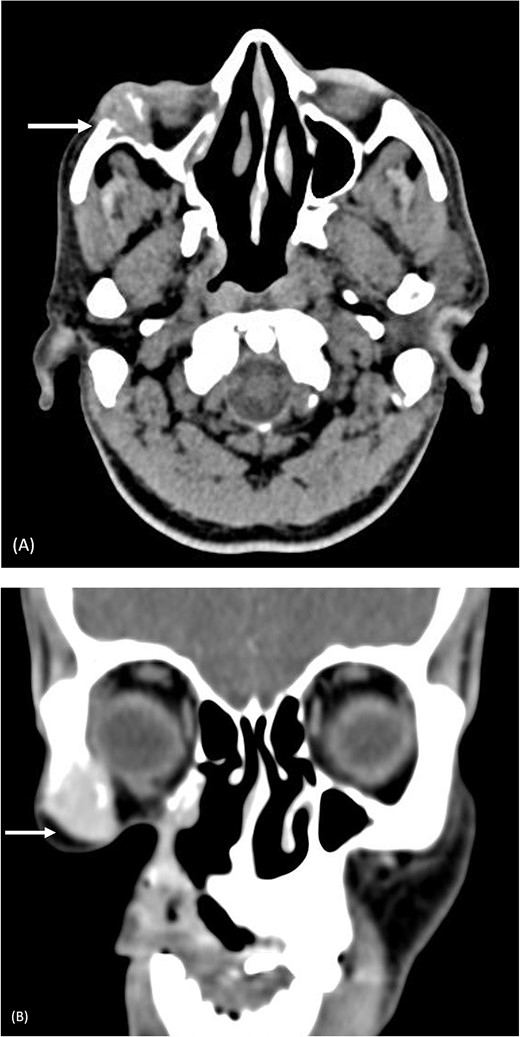

Fine needle aspiration cytology of the swelling revealed a malignant round cell tumor that was given the differential diagnosis of olfactory neuroblastoma. On computed tomography (CT), the lesion was causing erosion of the lateral wall of the right orbit and right zygomatic bone, with involvement of the lateral rectus muscle, shown in Fig. 1.

Pre-operative computed tomography of the zygomatic region. (A) Axial CT (bone algorithm) demonstrating a mass of size 2.2 × 2.1 × 2.1 cm3 in the right infraorbital region; (B) coronal CT (bone algorithm) demonstrating erosion of the lateral wall of the right orbit and right zygomatic bone, with involvement of the lateral rectus muscle.